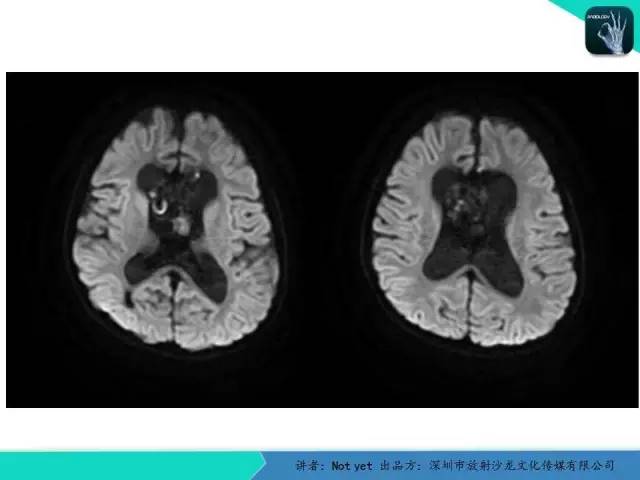

【病例】脑室内脉管瘤1例CT及MR影像诊断与鉴别